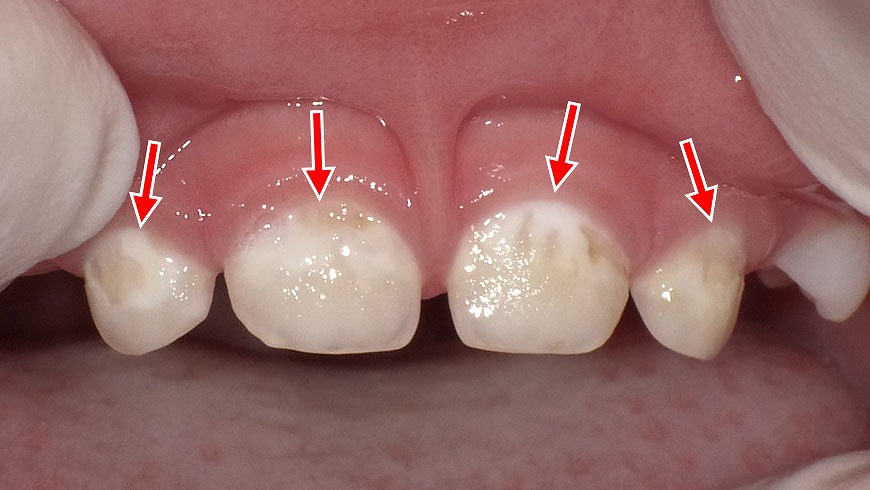

3歳児に見られる初期虫歯とプラークの付着

乳歯の表面や歯と歯ぐきの境目に、白っぽく見える部分が確認できます。これはプラーク(歯垢)がたまりやすい部位で、3歳前後の小さなお子さんでは「初期虫歯(う蝕)」が始まりやすいポイントです。

痛みがなくても進行することが多いため、仕上げ磨きの継続と早めの歯科受診が大切です。特に上の前歯は虫歯になりやすいため、毎日のケアと定期チェックが予防につながります。